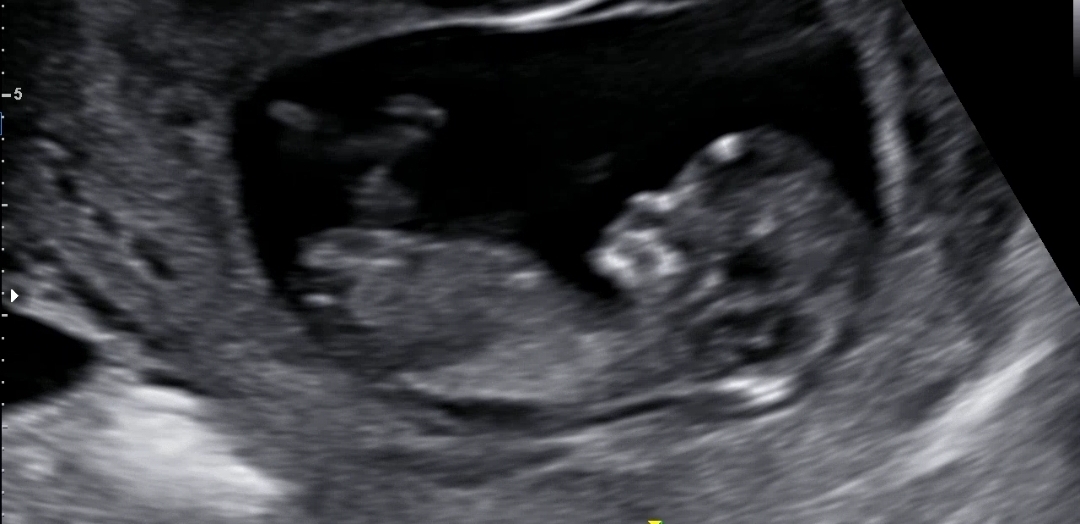

각도법 고수님들 저희아기도 봐주세요!! 11주3일

11주3일 아기 초음파에요 성별예측은 안해주셨어요 딸일까요 아들일까요?ㅎㅎ

다리사이 사진도올려요 가운데 뿔룩 나온건 탯줄이래요 이외 성별예측은 안해주시더라구요